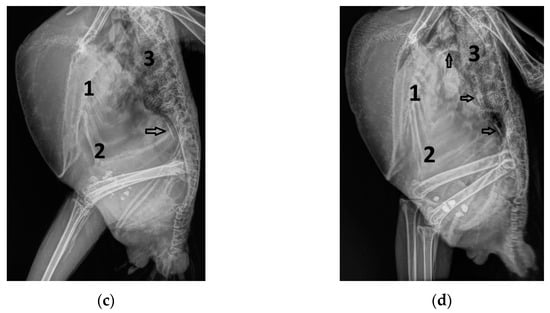

Figure 2.

Insufficiencies of the right (a) and left (b) atrioventricular valve and the pulmonary (c) and aortic valve (d) of Congo grey parrots, visualized by colour flow Doppler echocardiography. Arrow: marked insufficiency jet; RV: right ventricle; LV: left ventricle; RA: right atrium; LA: left atrium; AO: aorta; 1: right atrioventricular valve; 2: left atrioventricular valve; 3: pulmonary valve; 4: aortic valve. The colour scale on the right side of the image is calibrated in m s−1.

Figure 3.

Sonographic findings of Congo grey parrots: (a) Insufficiency of the right atrioventricular valve (AVright) due to an enlarged right ventricle, with PW Doppler sonographic diastolic blood flow profile of the AVright with a systolic insufficiency jet (I) with a very short acceleration phase; H: hepatoperitoneal cavity effusion. (b) End-diastolic movement of the septum in the direction of the left ventricle (arrow), as seen with B-Mode echocardiography; PE: pericardial effusion; RV: right ventricle; LV: left ventricle; RA: right atrium; LA: left atrium; AO: aorta; L: liver; 1: AVright. (c) B-Mode sonography of a congested liver associated with right heart failure, with compacted liver tissue and highly congested liver veins (V); H: hepatoperitoneal cavity effusion; PE: pericardial effusion. (d) B-Mode echocardiography of a liver with nodular liver tissue associated with the shape of the pulmonary blood flow profile, which had a short acceleration phase (outlier group 1).